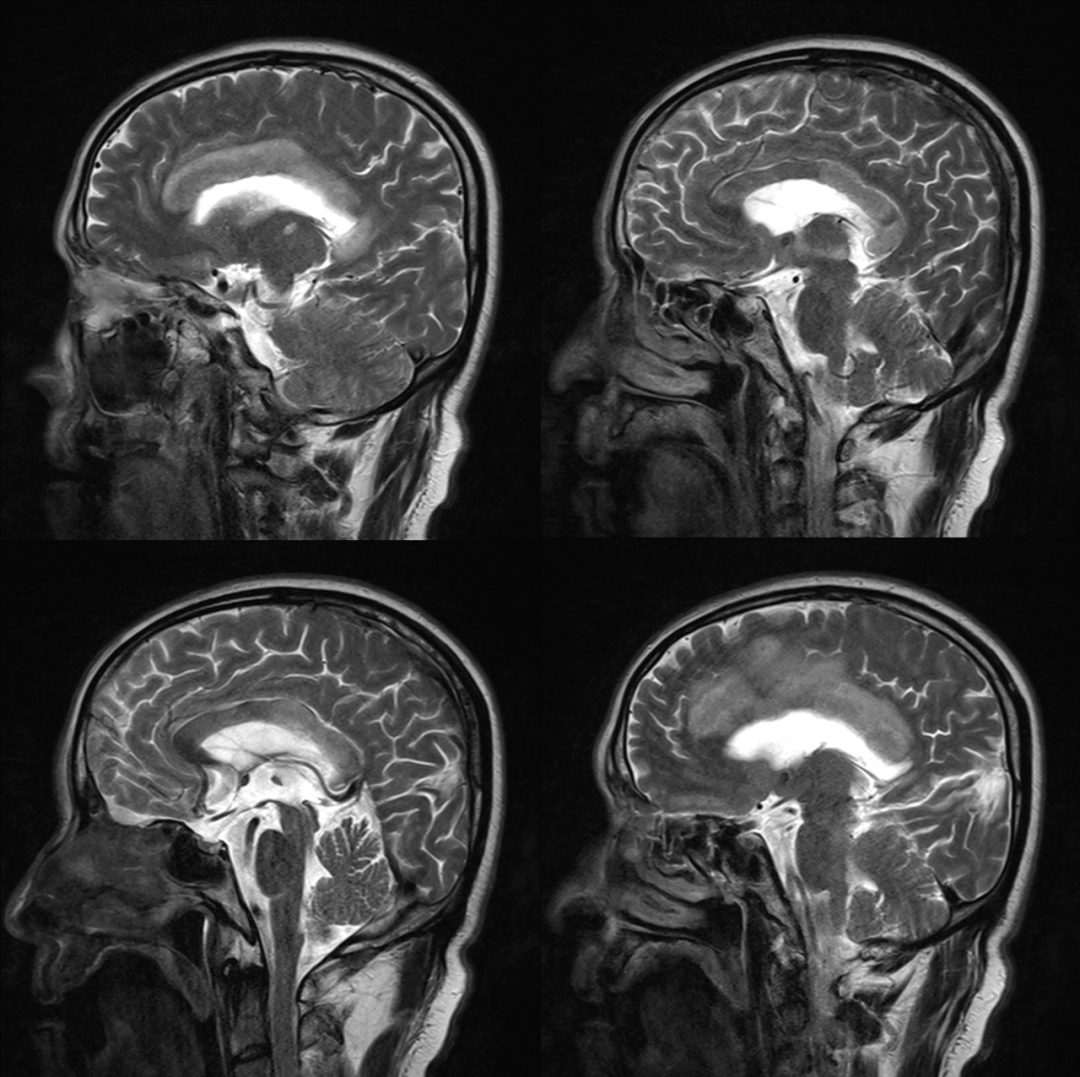

•急性期表现为胼胝体弥漫性肿胀,T1WI呈稍低信号,T2WI及FLAIR呈稍高信号,以矢状位观察最佳,可单独累及胼胝体压部或整个胼胝体,DWI呈高信号,ADC图呈低信号,部分患者可观察到脑室周围白质或内囊受累,少见皮层受累,表现为扩散受限,不强化和强化病例均可见到。如果增强扫描可见胼胝体有不同程度强化,呈小灶状或不规则斑片状,系血脑屏障破坏所致(如本例),本例患者处于急性期。

原发性胼胝体变性急性期:T2WI矢状位(A)清晰观察到弥漫胼胝体病变,FLAIR呈高信号(B),DWI呈高信号(C),ADC图呈低信号。